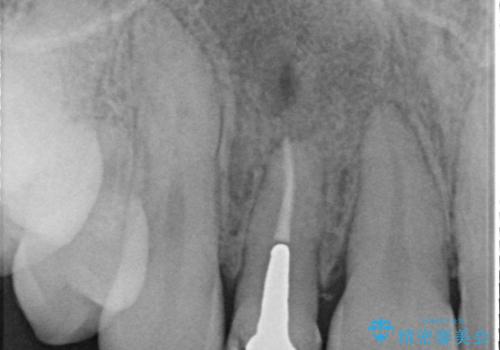

被せ物と歯の境の位置が歯肉の上に設定されており、それによって審美障害が起きていました。

歯と被せ物の境を歯肉縁下0.5㎜に設定して形成を行いオールセラミッククラウン(スペシャル)で治療を行いました。